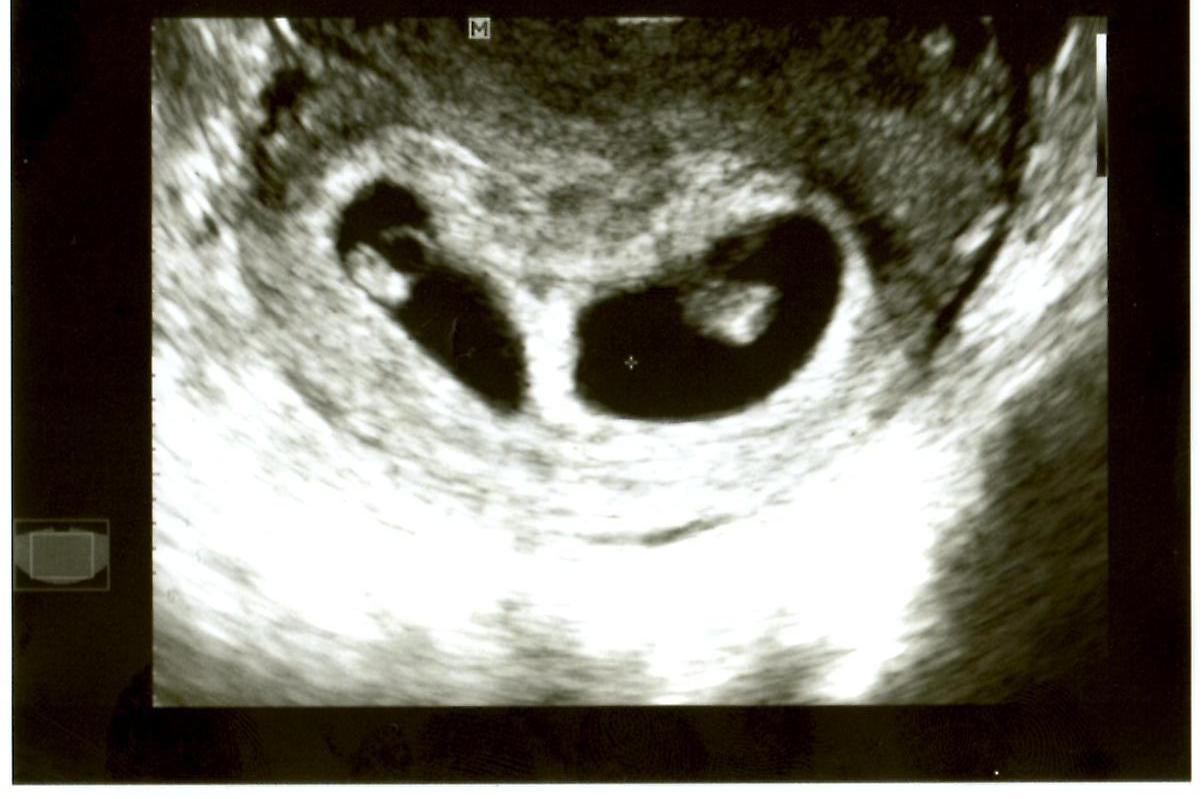

What Does A Vanishing Twin Look Like On An Ultrasound . an ultrasound is typically first performed between 8 and 12 weeks of pregnancy, during which time you might. since ultrasonography and transvaginal sonography. For example, a woman may have an ultrasound at 6 or 7 weeks gestation. this article will discuss how vanishing twin syndrome is detected on an ultrasound, the symptoms associated with having a. today, doctors diagnose vanishing twin syndrome by using ultrasounds. If your first ultrasound identified. vanishing twin syndrome (vts) is a miscarriage that causes a pregnancy involving twins to become a. The doctor identifies two fetuses, and the woman is told she is having twins. how will i know if i have a vanishing twin? When the woman returns for her next visit, only one heartbeat can be heard with a doppler. Most often, a vanishing twin is diagnosed during an ultrasound.

vanishing twin syndrome (vts) is a miscarriage that causes a pregnancy involving twins to become a. today, doctors diagnose vanishing twin syndrome by using ultrasounds. The doctor identifies two fetuses, and the woman is told she is having twins. how will i know if i have a vanishing twin? If your first ultrasound identified. When the woman returns for her next visit, only one heartbeat can be heard with a doppler. For example, a woman may have an ultrasound at 6 or 7 weeks gestation. Most often, a vanishing twin is diagnosed during an ultrasound. this article will discuss how vanishing twin syndrome is detected on an ultrasound, the symptoms associated with having a. since ultrasonography and transvaginal sonography.

What Does A Vanishing Twin Look Like On An Ultrasound For example, a woman may have an ultrasound at 6 or 7 weeks gestation. this article will discuss how vanishing twin syndrome is detected on an ultrasound, the symptoms associated with having a. how will i know if i have a vanishing twin? an ultrasound is typically first performed between 8 and 12 weeks of pregnancy, during which time you might. The doctor identifies two fetuses, and the woman is told she is having twins. For example, a woman may have an ultrasound at 6 or 7 weeks gestation. Most often, a vanishing twin is diagnosed during an ultrasound. When the woman returns for her next visit, only one heartbeat can be heard with a doppler. today, doctors diagnose vanishing twin syndrome by using ultrasounds. since ultrasonography and transvaginal sonography. If your first ultrasound identified. vanishing twin syndrome (vts) is a miscarriage that causes a pregnancy involving twins to become a.